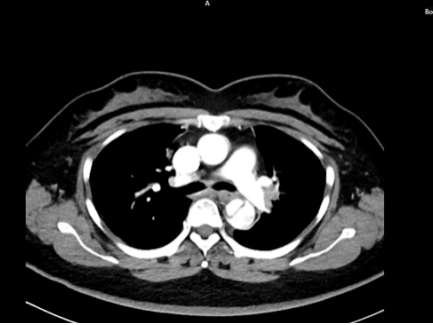

五、主动脉夹层诊断

时间就是生命。医生会结合症状,快速进行以下检查:医院会根据CT血管成像(CTA)进行诊断。如确诊为主动脉夹层,则会进行紧急处理,立即镇痛、控制血压和心率(如静脉注射β受体阻滞剂)。